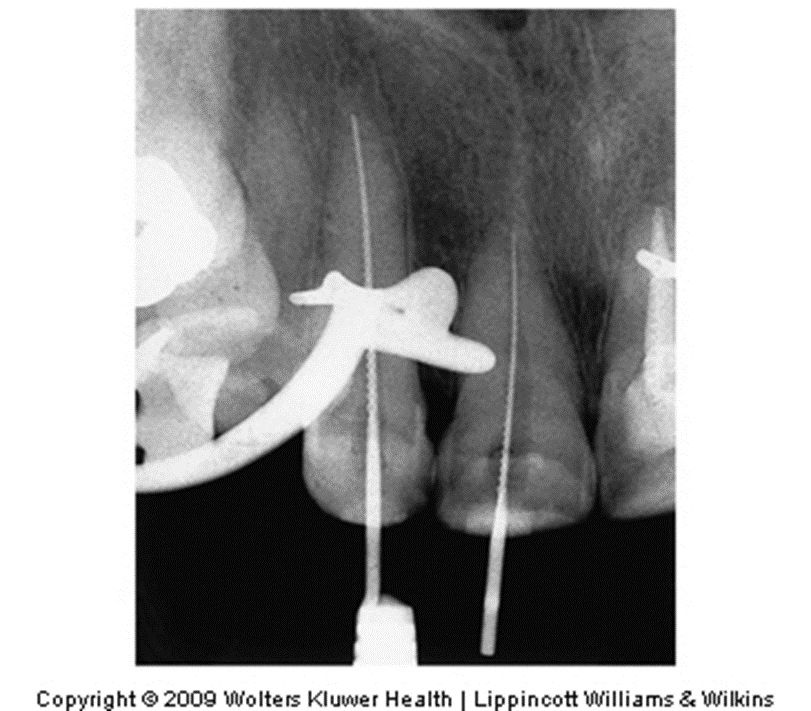

What material is being placed inside the pulp of this xray?

Answer: Endodontic File

Used to clean (remove necrotic tissues inside the canal), shape, and smooth the canal.